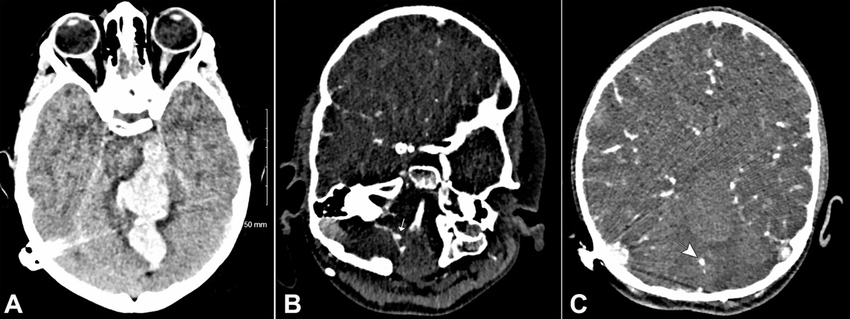

18 months after the first hospital admission, she experienced sudden onset severe headache, one grand mal seizure lasting 3 minutes, and vomiting, at rest, followed by loss of conscious level - best GCS 04/15 (E2V1M1). She was intubated on scene and an immediate CT head depicted a large intracranial hemorrhage centered onto the cerebellar vermis and extending into the brainstem, ventricular system, the quadrilateral cistern, and the left cerebral peduncle, with adjacent vasogenic edema. CT angiogram revealed another proximal right PICA aneurysm and a further superior cerebellar artery aneurysm (Figures 33B, and 3C).

A CT angiogram (CTA) revealed a ruptured aneurysm of the posterior inferior cerebellar artery (PICA) branch. An external ventricular drain (EVD) was inserted for intracranial pressure (ICP) control, and she was admitted to PICU. The aneurysm was coiled, the hematoma evacuated, and a digital subtraction angiography (DSA) revealed an aberrant branch of PICA with a distal aneurysm (Figures 2A and 2B).